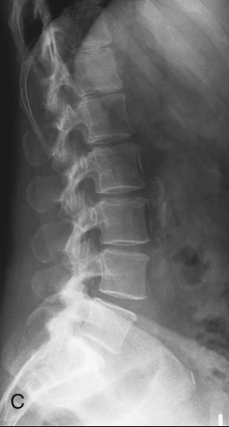

Lateral L-Spine: Is this Image Good?

No

Note: There are 6 lumbar vertebrae

Rotation and tilt begin in L4 and gets progressively worse as you move up the spine

Stack the hips and shoulders (fixes rotation) and place a support sponge under the waist (fixes tilt)

Overexposed; loss of contrast; decrease kVp

Marker cut-off